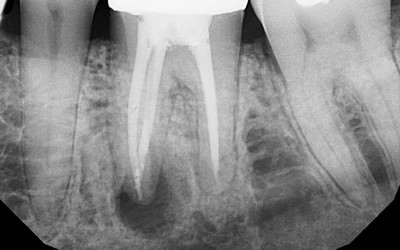

- Оценка результатов обследования, состоящего из осмотра ротовой полости, перкуссии, пальпации, зондирования входа в канал, температурных тестов, определения подвижности проблемного зуба, применения электроодонтодиагностики и радиовизиографии, проведения рентгенографии.

Важно! Данные, полученные при помощи рентгена, показывают полноценную картину заболевания. Насколько точно они будут расшифрованы — зависит от опытности врача.

- Контролировать свои действия с помощью рентгена.

Является обязательным условием. Только после того, как будет поставлена временная пломба, проведён рентген, можно ставить постоянную.

- Проверить результат с помощью рентгена.